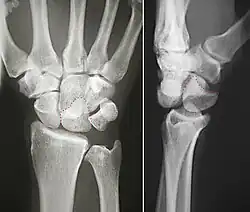

Das Mondbein kann an einer Arthrose des Handgelenks beteiligt sein. Selten kommt es bei Stürzen zu einer „perilunären Luxation“, bei der die übrigen Handwurzelknochen vom Mondbein abreißen, das fest mit Speiche und Elle verbunden bleibt. Unfallbedingt oder rheumatisch verursacht kann es zur Destruktion von Bändern mit einer „skapholunären Dissoziation“ kommen, bei der auf Röntgenaufnahmen eine typische Lücke zwischen Kahnbein und Mondbein zu erkennen ist.